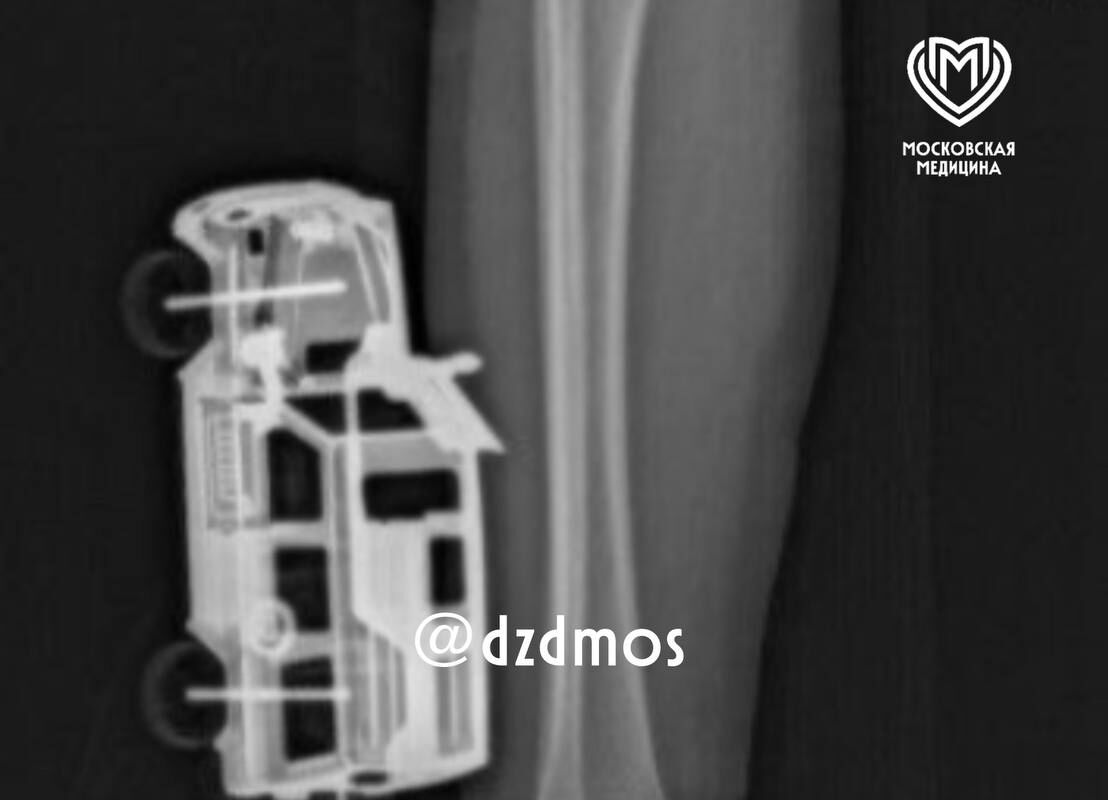

В Москве четырехлетний мальчик упал на игрушечную машинку и оказался в больнице. Об этом сообщает Telegram-канал «Московская медицина».

По словам родителей, ребенок прыгнул с кровати у себя дома и неудачно упал на игрушку правой голенью. Машинка повредила мягкие ткани, ее части вошли глубоко и достигли подкожножировой клетчатки.

Пострадавшего мальчика доставили в больницу, где ему сделали рентген, чтобы исключить повреждение костей. После этого медики удалили игрушку и провели хирургическую обработку образовавшейся на ноге ребенка раны. Через сутки малолетнего пациента уже выписали домой.